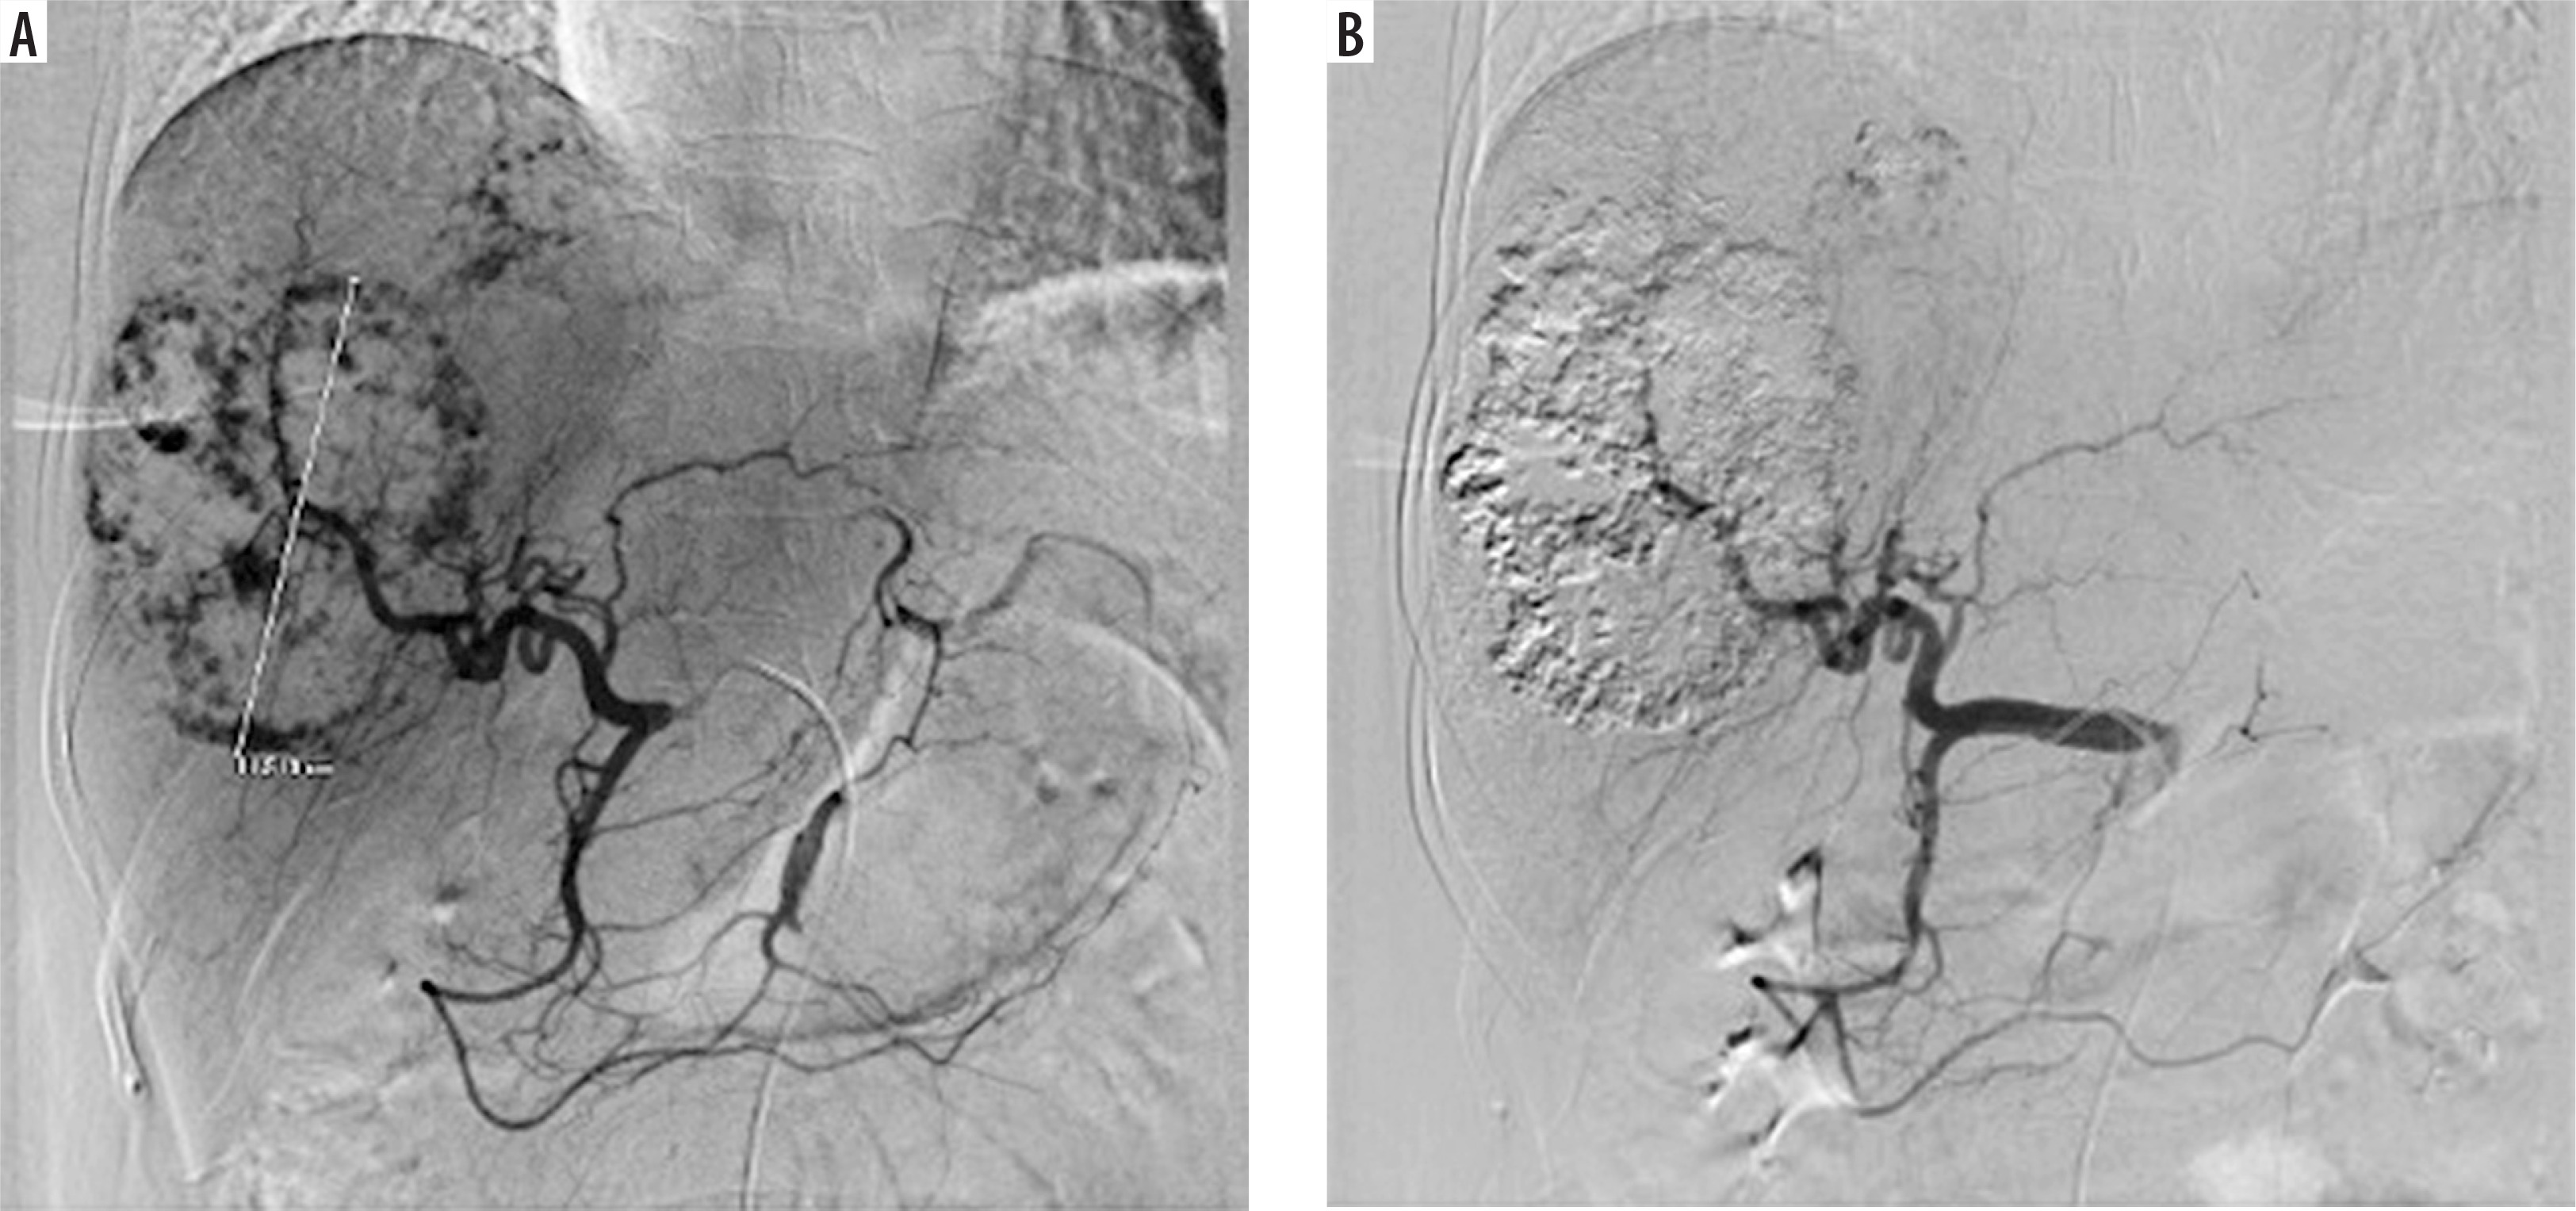

Under fluoroscopy, a water-in-oil (W–O) emulsion containing 15 IU of bleomycin powder (medac GmbH, Wedel, Germany) dissolved in 5 cc of normal saline was mixed with 10 cc of lipiodol (Guerbet, Villepinte, France) using standard 3-way stopcocks, followed by a slow injection into the artery feeding the haemangioma. According to the protocol, one dose of the emulsion was administered. The embolisation end point was blood stasis of the tumour-feeding arteries (Figure 1).